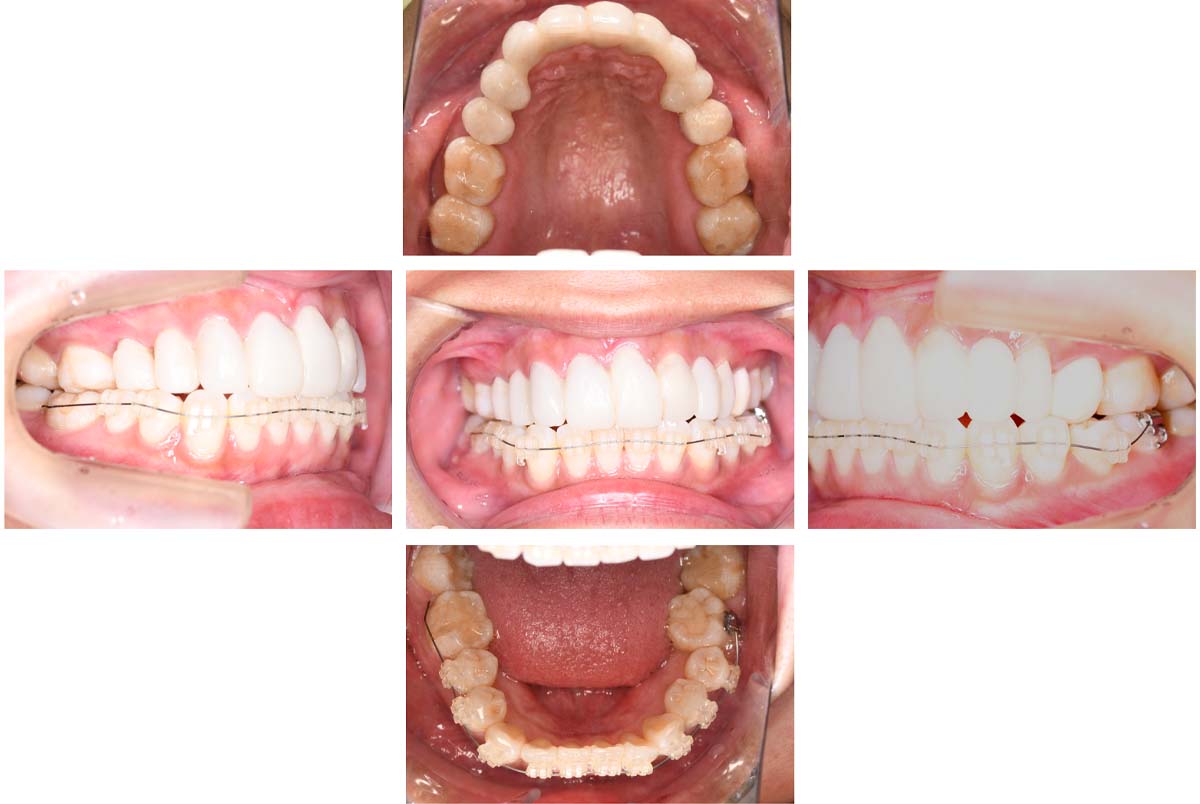

| 治療内容 | ①スプリントを装着 ②副子を装着 ③2024年4月 口腔内反映開始 ④副子を入れた状態の所まで咬合を挙上 (バイトアップ) ⑤2024年5月 上顎前歯部8本へ仮歯(TEK) を装着 |

2024年 10月 下顎MTM開始